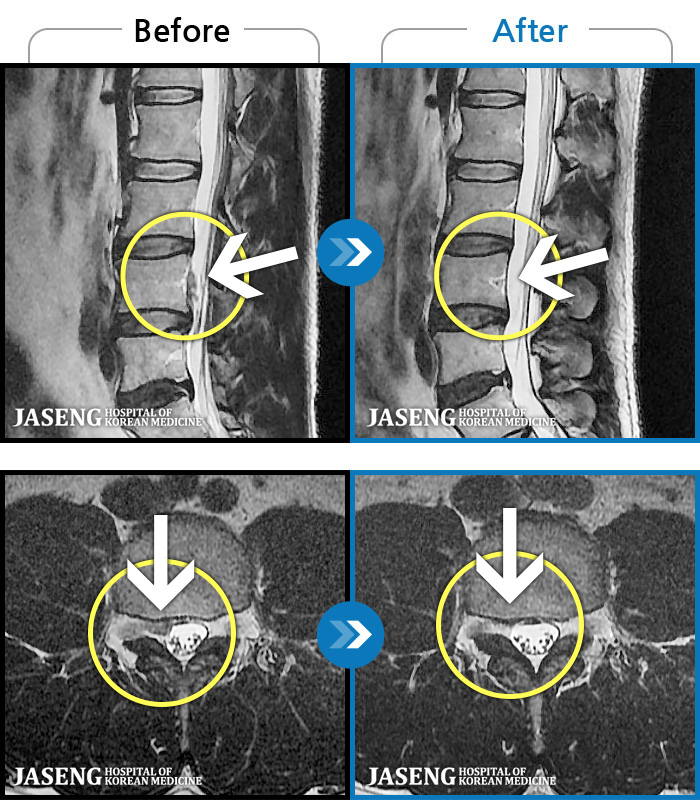

ȯںп Ǹ ǿ ԿǾ, ο ġ ۿ Ƿ ġḦ Ͻñ ٶϴ.